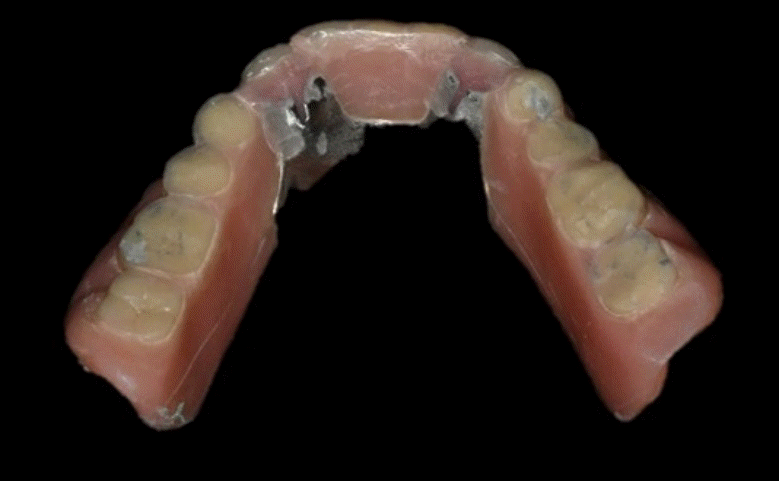

Fig. 2.

Denture wear is detected in posterior area of old denture. RPD is converted into complete denture after extraction of both canine.

본 증례는 44세 여환으로, 하악 의치가 계속 탈락하여 재제작을 원한다는 주소로 내원하였다. 상악은 고정성 수복물, 그리고 하악은 총의치를 착용 중이었고 하악 양측 구치부의 심한 골 흡수로 인해 유지력 소실로 불편감을 호소하였다. 3개월 전 하악 양측 견치를 발거한 이후로 하악 국소의치를 총의치로 전환하였고, 총의치는 구치부의 심한 교합면 마모와 의치의 후방부가 후구치 삼각 융기를 피개하지 않는 형태였다. 전신 병력으로는 지적장애 및 골관절염으로 약 2개월 간 약물 복용 중이었다. 상악 우측 제1대구치와 제2대구치, 제1소구치 그리고 제2소구치는 우식이 진행된 상태였고, 우측 제2소구치와 우측 제1대구치는 근관치료가 완료된 후 수복되지 않은 상태였다. 상악 좌측 제1소구치와 제2소구치, 그리고 제1대구치 수복물 하방으로 이차 우식이 진행된 상태였고, 전체적으로 교합평면이 균일하지 않은 형태였다(Figs. 1-3).상악 우측 구치부의 수복되지 않은 치아와 상악 좌측 보철물 하방의 이차 우식이 있는 치아는 모두 우식 제거가 필요하여 양측 구치부 각각 3개의 치아는 재수복을 결정하였고, 하악은 구치부의 심한 치조골 흡수로 인해 의치 사용은 불가할 것으로 판단하여 전방부에 임플란트를 식립하여 구치부는 캔틸레버 형태를 가지는 all-on-X 수복을 계획하였다. 의치의 수직고경에 맞춰 교합 평면을 균일하도록 하여 왁스업 시행하였고(Fig. 4), 이후 적절한 교합 수직 고경의 임시 의치를 제작하였다. 약 2개월의 적응기간을 거쳐 의치 적응도와 수직 교합 고경을 평가하였고 적절한 기능과 심미를 확인하였다. 상악 우측 제1소구치와 제2소구치, 제1대구치 그리고 상악 좌측 제1소구치와 제2소구치, 제1대구치는 우식을 제거한 다음, 임시 보철물로 재수복하여 적절한 교합 평면을 설정하였다(Fig. 5).환자가 적응한 임시 의치를 모델 스캔(Medit T710, Medit, Seoul, Korea)하여 프린팅용 레진(Graphy Tera Harz SG-100, Graphy, Seoul, Korea)을 이용하여 3D 프린팅하였고, 출력된 의치에 방사선 불투과성 레진(G-æenial Universal Flo, GC, Luzern, Swiss)을 부착하여 레진 마커를 형성하였다. 레진 마커를 부착한 프린팅 의치를 장착한 채로 콘빔 전산화 단층촬영(CBCT, R2 Studio Q, Megagen, Seoul, Korea)를 촬영하였다(Fig. 6). 촬영한 CBCT 데이터와 의치 스캔 파일을 중첩하여 CAD 소프트웨어(R2 Studio Q, Megagen, Seoul)를 통해 이상적인 임플란트 식립을 계획하였다. 전후방 거리를 연장하여 적절한 캔틸레버를 부여하기 위해 전방부에 3개의 임플란트를 식립하고, 양측 후방부에는 약 30도 경사진 임플란트를 식립하도록 계획하였다(Fig. 7).가이드는 상악의 자연 치열과 대합되는 의치 복제 형태의 상부 가이드, 그리고 가이드 핀이 존재하는 하부 가이드로 이루어지도록 디자인되었다(Fig. 8). 상부 가이드는 임시 의치의 스캔 데이터를 이용해 상부 가이드의 하부면과 하부 가이드의 상부면이 장착되어 구내에서 적합될 수 있도록 CAD 소프트웨어(Meshmixer, Autodesk, San Francisco, CA, USA) 상에서 디자인되었다. 임시 의치의 하부면과 하부가이드의 하부면을 치은과 중첩시켜 어버트먼트의 위치에 홀을 형성한 다음 3D 프린팅(Graphy Tera Harz SG-100, Graphy, Seoul, Korea) 하였다. 수술 당일 장착될 임시 보철물 또한 동일한 CAD 소프트웨어를 통해 제작하였다.수술 당일 이중 가이드를 구내에 장착하여 하부가이드를 고정 핀으로 고정시킨 후(Fig. 9), 계획된 위치에 임플란트 고정체를 식립하였다. 임플란트는 5개 모두 외부 연결형 고정체(AnyOne External, Megagen, Seoul, Korea)를 사용하였고, 식립 시 식립 토크는 모두 40N 이상, ISQ는 70이상으로 양호한 초기 고정력을 확보하였다(Fig. 10). 즉시 부하를 위해 기성 어버트먼트를 체결하였고, 임시 보철물을 장착하여 양측 소구치부에서의 균일한 교합을 확인하였다(Fig. 11).임플란트 주위 골과 치은의 회복을 위해 약 2달간 임시 보철물을 경과 관찰하였고, 이후 최종 보철을 위한 인상 채득을 시행하였다. 상하악 임시 보철물을 장착한 중심교합 상태에서 구내 스캔(Trios 4, 3 Shape, Copenhagen, Denmark)을 시행하여 악간 관계를 채득하였다(Fig. 12). 임시 보철물을 제거한 상태에서 하악의 전방부 3개의 임플란트에 scan body(Scan Abutment, Megagen, Seoul, Korea)를 연결하고, 양측 최후방 임플란트 2개에는 각각 Ti base multi-unit abutment(multi-angled abutment, Osstem, Seoul, South of Korea)를 30Ncm으로 체결한 후 multi scan body(TS Multi scanbody, Osstem, Seoul, Korea)를 연결하여 구내 스캔(Trios 4, 3Shape, Copenhagen, Denmark)을 시행하였다. 이후 스캔 바디를 연결하여 채득한 스캔 파일을 상하악 임시 보철물 상태에서 채득한 스캔 파일과 중첩하여 CAD 소프트웨어(exocad GmbH, Darmstadt, Germany)에서 최종 보철물을 디자인하였다(Fig. 13).최종 보철물은 양측 최후방 임플란트 고정체에 각각 Ti-base(TS multi Ti base, Osstem, Seoul, Korea)와 접착된 나사 유지형 단일 지르코니아 크라운으로, 지르코니아 블록(Zircen, Kuwotech, Gwangju, Korea)을 밀링하여 제작하였고, 치경부 하방으로 포세린으로 치은 형태를 부여하였다. 전방부 3개의 임플란트 고정체에는 맞춤형 지대주를 제작하여 30N으로 체결하였고, 양측 최후방 고정체는 20Ncm으로 체결한 후 레진 시멘트(Rely X U200; 3M ESPE, St. Paul, MN, USA)로 접착 시행하였다. 장착 후 중심교합시 양측의 제1대구치 부위에서 교합력이 적게 가해지도록 교합 조정 시행하였으며, 전방과 측방운동시에 임플란트 상호보호교합이 되도록 조정하였다. 또한 연결부 하방으로 치실을 통과시켜 치은 점막 사이 공간을 평가하였으며, 구강 위생 관리의 용이성을 확인하였다. 이후 1주, 1개월, 3개월 경과 관찰하였고, 환자는 저작이나 심미, 발음 등에서 만족해하였다(Figs. 14 and 15).